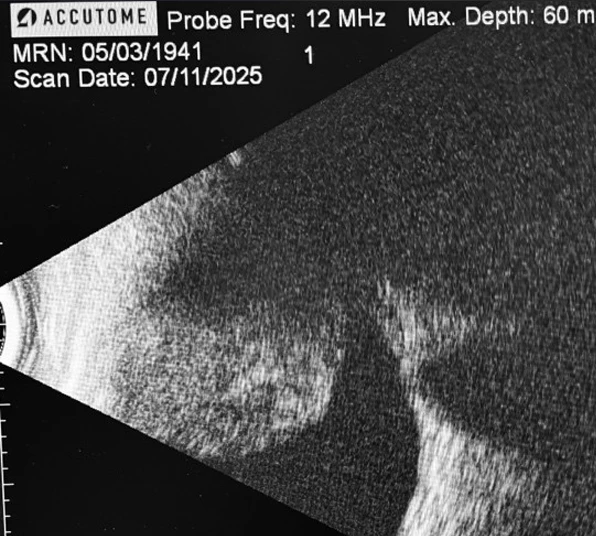

On further examination the patient was found to have a large pigmented choroidal mass taking up most of the superior fundus. B-Scan ultrasound displayed a large choroidal mass with low internal reflectivity a finding highly correlated with choroidal melanoma. Prognosis depends on tumour size, cytogenetic profile, and presence of metastases, with the liver being the most common site of distant spread.

B-Scan ultra sound displaying a large choroidal lesion with low internal reflectivity – consistent with a choroidal melanoma